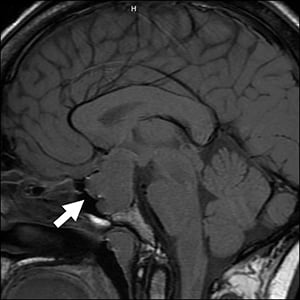

Dopamine agonists have been used in the treatment of acromegaly, but they are modestly effective and are rarely associated with impulse control disorders (ICDs). We present the case of a 34-year-old woman with acromegaly who underwent transsphenoidal resection for an invasive pituitary macroadenoma, followed by the development of panhypopituitarism. Postoperative imaging revealed residual tumor, and her insulin-like growth factor I levels remained elevated, indicating disease persistence. She subsequently received salvage radiosurgery and was treated with lanreotide and cabergoline, achieving biochemical control of her disease. The patient later reported frequent adrenal crisis episodes with worsening anxiety. Four years after initiating cabergoline, she disclosed impulse control behaviors, including pathological gambling, which had resulted in financial stress and emotional strain. Two weeks after discontinuing cabergoline, she had complete resolution of her ICD symptoms with improved anxiety levels and fewer adrenal crisis episodes. In this case, cabergoline-induced gambling contributed to psychosocial stress that likely exacerbated her adrenal crisis episodes. Our case emphasizes the need for routine behavioral screening in patients treated with dopamine agonists. Early identification and discontinuation or dose reductions of dopamine agonists is recommended to allow for ICD resolution and consequently, reducing the risk of exacerbating adrenal crisis episodes.